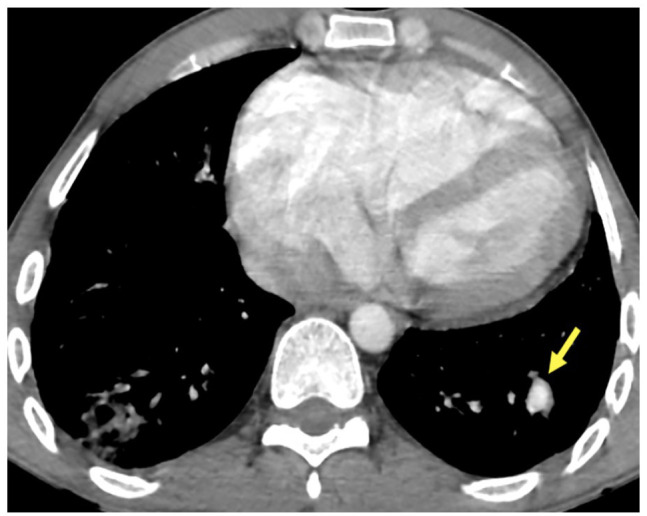

Case presentation: We present the case of a 32 year old male with known history of congenital ventricular septal defect presented to the emergency department with signs of sepsis and dyspnea. Blood cultures were positive for methicillin-sensitive Staphylococcus aureus. An echocardiogram found evidence of endocarditis with multiples intra cavitary vegetations. A CT angiogram demonstrated major right ventricular dilatation, multiple nodules and peripheral opacities, scattered throughout the lungs, indicative of septic emboli. Segmental saccular dilatation of the left lateral basal pulmonary artery consistent with a mycotic aneurysm formation was found. The patient was started on intravenous antibiotics and given the overall satisfactory evolution a conservative approach was pursued. The patient was discharged with antibiotics and scheduled for surgical repair of the ventricular septal defect.